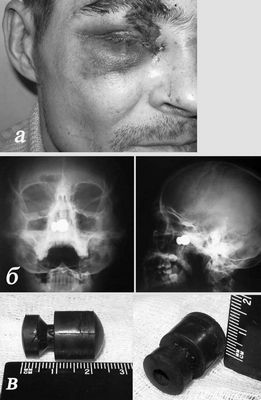

Устройство давления, которое носят на ухе ночью, чтобы лечить проанализированную рубцовую ткань

Расследование семи больных проанализировало применение устройства давления, которое носят скоро, дабы подкрепить другую терапию для ушных келоидов (наращивание рубцовой ткани уха), сообщался в статье, опубликованной Онлайн Сперва сейчас Архивами Лицевой Пластической хирургии, одним из изданий JAMA/Archives. …